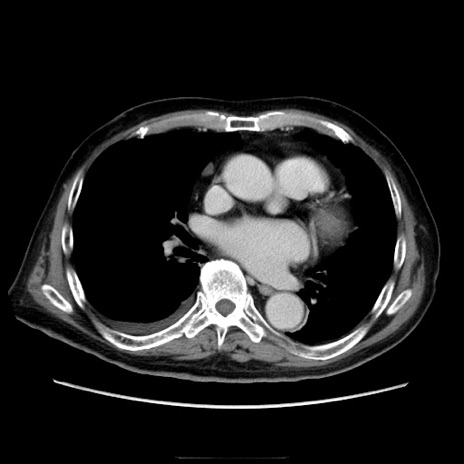

症例21(横断像)

【症例】70歳代男性

【主訴】腹痛

【現病歴】肝硬変・肝細胞癌にてかかりつけの方。約9時間前に食後より腹痛出現。症状が徐々に増悪し、嘔吐出現したため来院。

【既往歴】肝硬変、肝細胞癌(RFA、TACE後)

【身体所見】意識清明、表情苦悶様、BT 36℃、BP 129/78mmHg、P 88bpm、SpO2 97%(RA)、右上腹部から心窩部にかけて圧痛あり、反跳痛なし、筋性防御あり。

【データ】WBC 5800、CRP 0.16